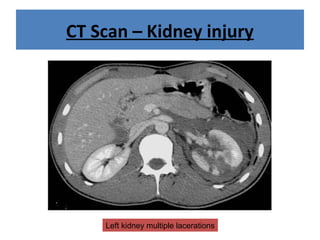

CT Scan – Kidney injury

Left kidney multiple lacerations

CT Scan –Kidney injury Left kidney multiple lacerations